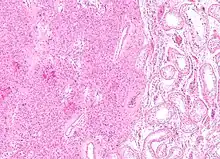

| Histopathology of a Leydig cell tumor, high magnification, H&E stain, showing typical features.[1] | |

A conclusive diagnosis is made via histology, as part of a pathology report made during or after surgery. Reinke crystals are classically found in these tumours and help confirm the diagnosis, although they are seen in less than half of all Leydig cell tumours. Immunohistochemical markers of Leydig cell tumours include inhibin-alpha, calretinin, and melan-A.[6]